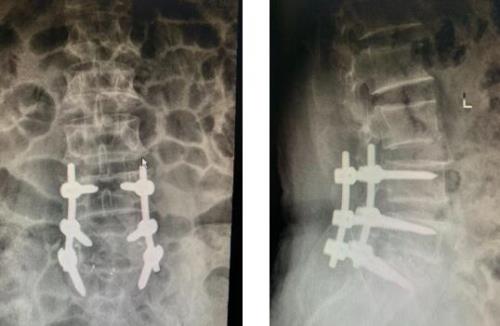

罗某,男,67岁,腰部疼痛伴右下肢放射痛、麻木2年余,间隙性破行半年。结合患者病史、症状体征及影像学检查后,诊断为腰椎管狭窄症(L4/5,L5/S1椎管狭窄)。在陆耀宇主任医师协助下,杨通宇主任医师为患者施行L4/5及L5/S1 MIS-TLIF。术后患者腰部及下肢症状明显缓解。

陆某,男,64岁, 反复腰部疼痛2年,加重伴双下肢疼痛麻木1+月, 诊断为腰椎管狭窄伴腰椎失稳,腰椎间盘突出, 在微创通道下行腰3/4、4/5 、腰5骶1 MiS-TLiF,术中出血少,术后恢复良好。

单节段腰椎微创融合手术仅需要2个约3cm的切口即可完成手术,双节段腰椎微创融合手术仅需要2个约4.0cm的切口即可完成手术经肌肉间隙入路,三个节段选择从症状重的一侧入路为主,达到创伤最小化的目的。因此Mis-TLIF手术不容易出现切口不愈合及伤口感染的风险。相比于侧路与前路手术,该术式能对病变节段硬膜囊进行直接减压,适用于需要接受直接减压的患者。与传统开放手术相比,肌肉、韧带损伤更少。该患者术后第2天即下床活动,伤口拆线后自行出院回家。